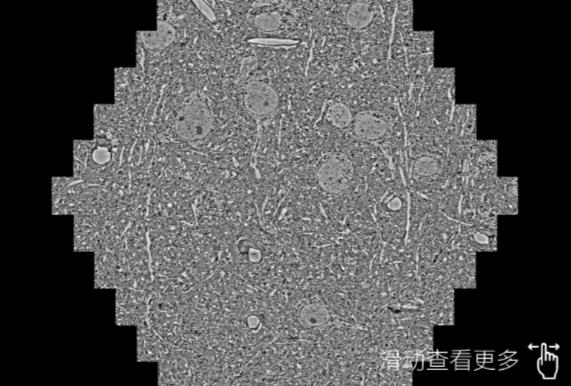

鼠脑切片。左图使用红桥蔡司红桥扫描电镜MultiSEM706对165μmx143pm面积区域成像,耗时仅需1.5秒。右图为鼠脑切片中30μm区域放大效果。样品由芝加哥大学B.Kasthuri提供。

使用蔡司高速红桥扫描电镜MultiSEM对1mm²人脑皮层组织进行高分辨成像,并对其中的各种细胞结构进行三维重构分析。左图展示了2x3mm²组织平面中锥体神经元的三维重构效果。右图显示了局部体积神经元三维重构。图像由哈佛大学chtman实验室提供,渲染图由D. Berger 制作。